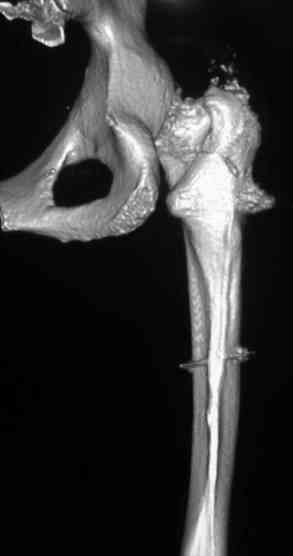

Уважаемые коллеги.Представляю, в качестве обратной связи, результат операции случая, о котором шла речь в сообщении от 14.01.

Присоеденюсь к поздравлениям, картинка красива. Гвоздь PFN-a Syntez? Мы взяли бы DePuy Affixus в длинной версии, в пользу большей ротационной стабильнсти головки.

Операция выполнена закрыто. Гвоздь PFNA, Synthes. Диаметр ножки 9 мм, клинок 100 мм. Перелили эр-массы 300 и еще плазмы литр. Кровотечения во время операции не было, но, поскольку при поступлении у пациентки гемоглобин был 50, чему объяснения так и не нашли, заказали на операцию побольше. А раз заказали, нужно перелить. Обратно у нас не принимают. Да и на пользу пошло безусловно.

Про влияние динамического скольжения клинка на сращение надеюсь не узнаем: о ранней нагрузке на фоне внутрисуставного перелома проксимального конца большеберцовой кости этой же ноги и перелома обеих лонных костей речь вряд ли пойдет. А к тому времени, когда начнем нагружать ногу (ориентировочно - 1.5 мес.), подвижности отломков уже не должно быть.